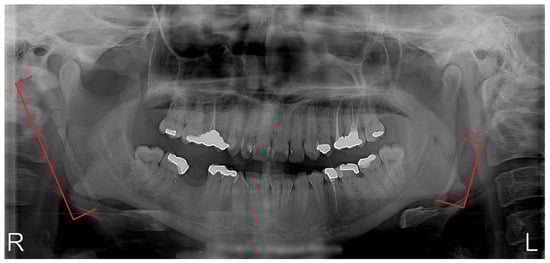

2. Material and Methods

3. Results